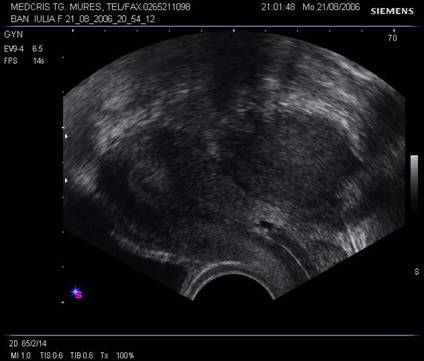

Tumorile ovariene

Ecografia abdominala si transvaginala trebuie sa raspunda suspiciunilor legate de malignitate sau benignitate. In functie de tipul de ecogenitate interna, tumorile ovariene se pot clasifica in [2,5,6] :

tumori ovariene pur chistice

tumori ovariene pur solide

tumori mixte ovariene

Criteriile de evaluare sonografica a acestora sunt:

Tumori ovariene chistice